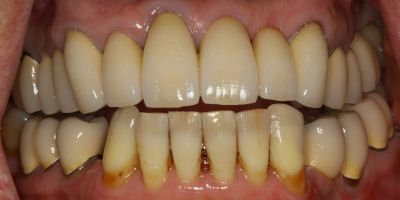

Before/After